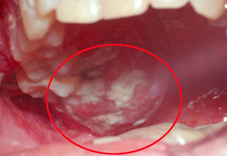

圖二及圖三、口腔或舌頭的內壁上會出現白色或紅色斑塊

■ 口腔或舌頭的內壁上會出現白色或紅色斑塊(如圖二、圖三)。